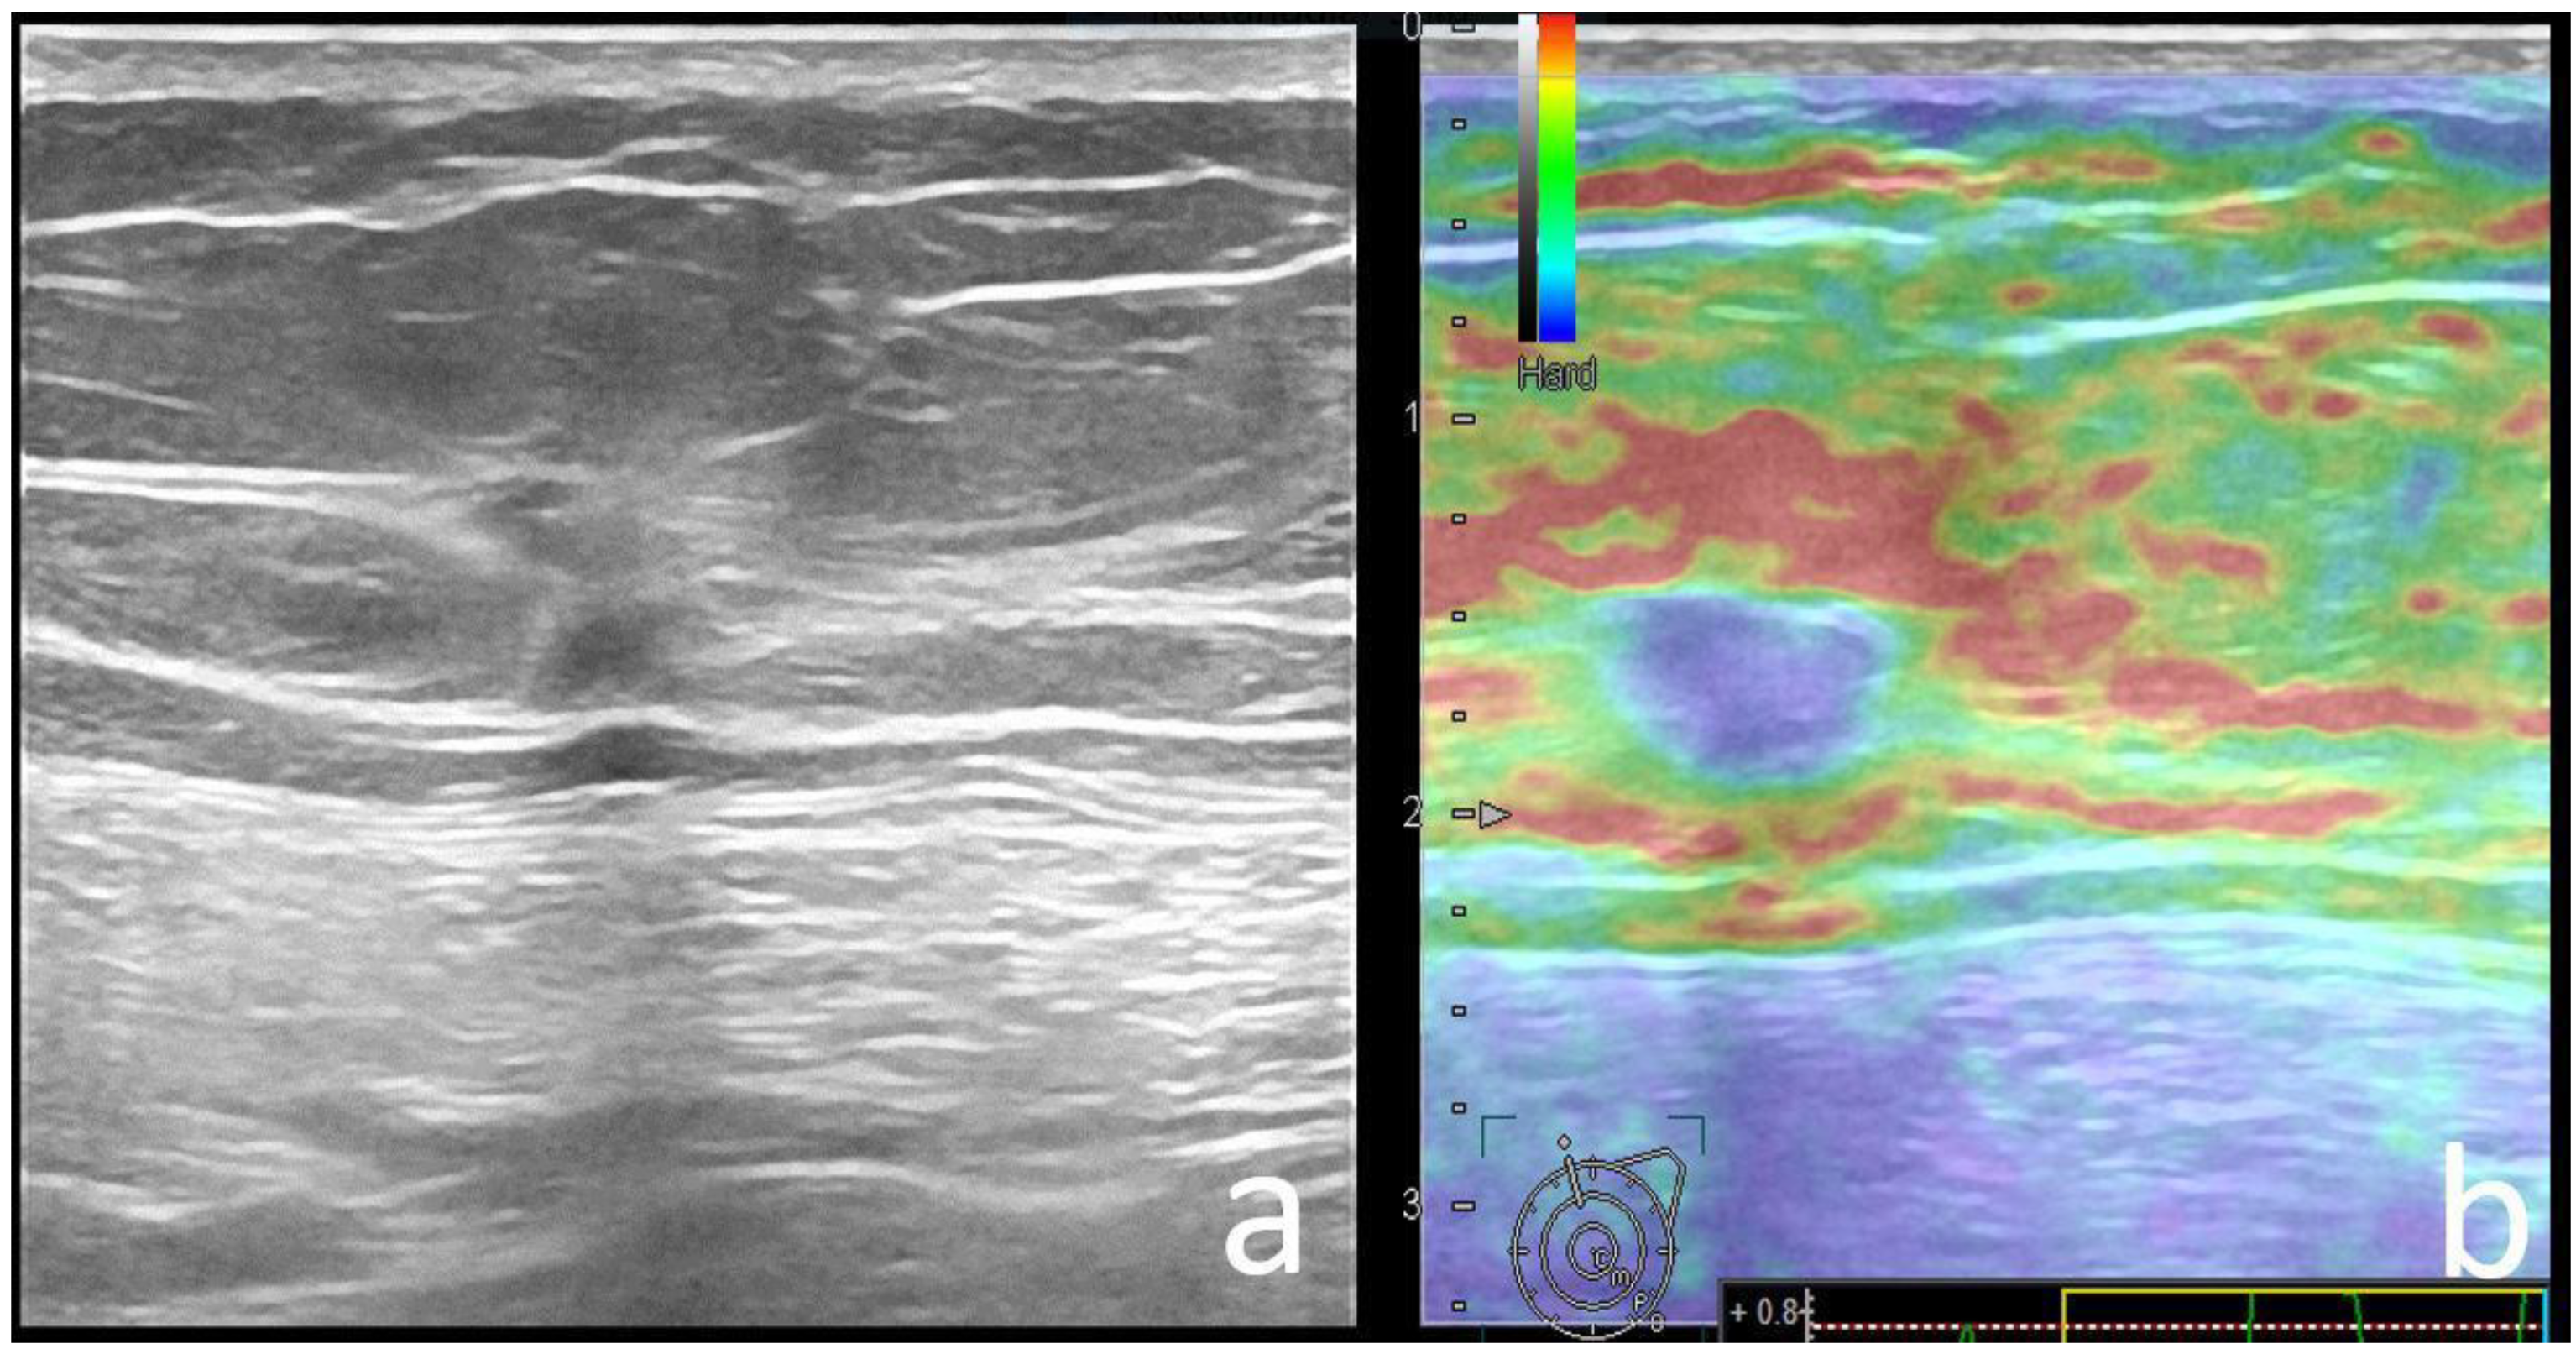

| Strain Elastography | 0.029 | ||

| Soft | 40 (40), 9 BGR | 30 (20.6), 1 BGR | |

| Hard | 58 (60) | 115 (79.3) | |

| BGR | blue-green-red elastography appearance |